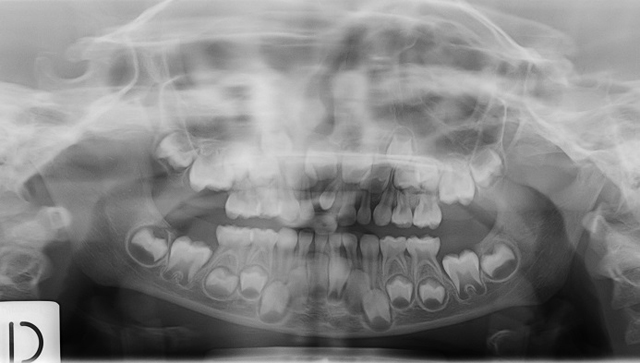

Caso 1: dente del giudizio inferiore sinistro

Caso 2: dente sovrannumerario in posizione incisiva superiore

Caso 3: dente sovrannumerario in posizione incisiva superiore